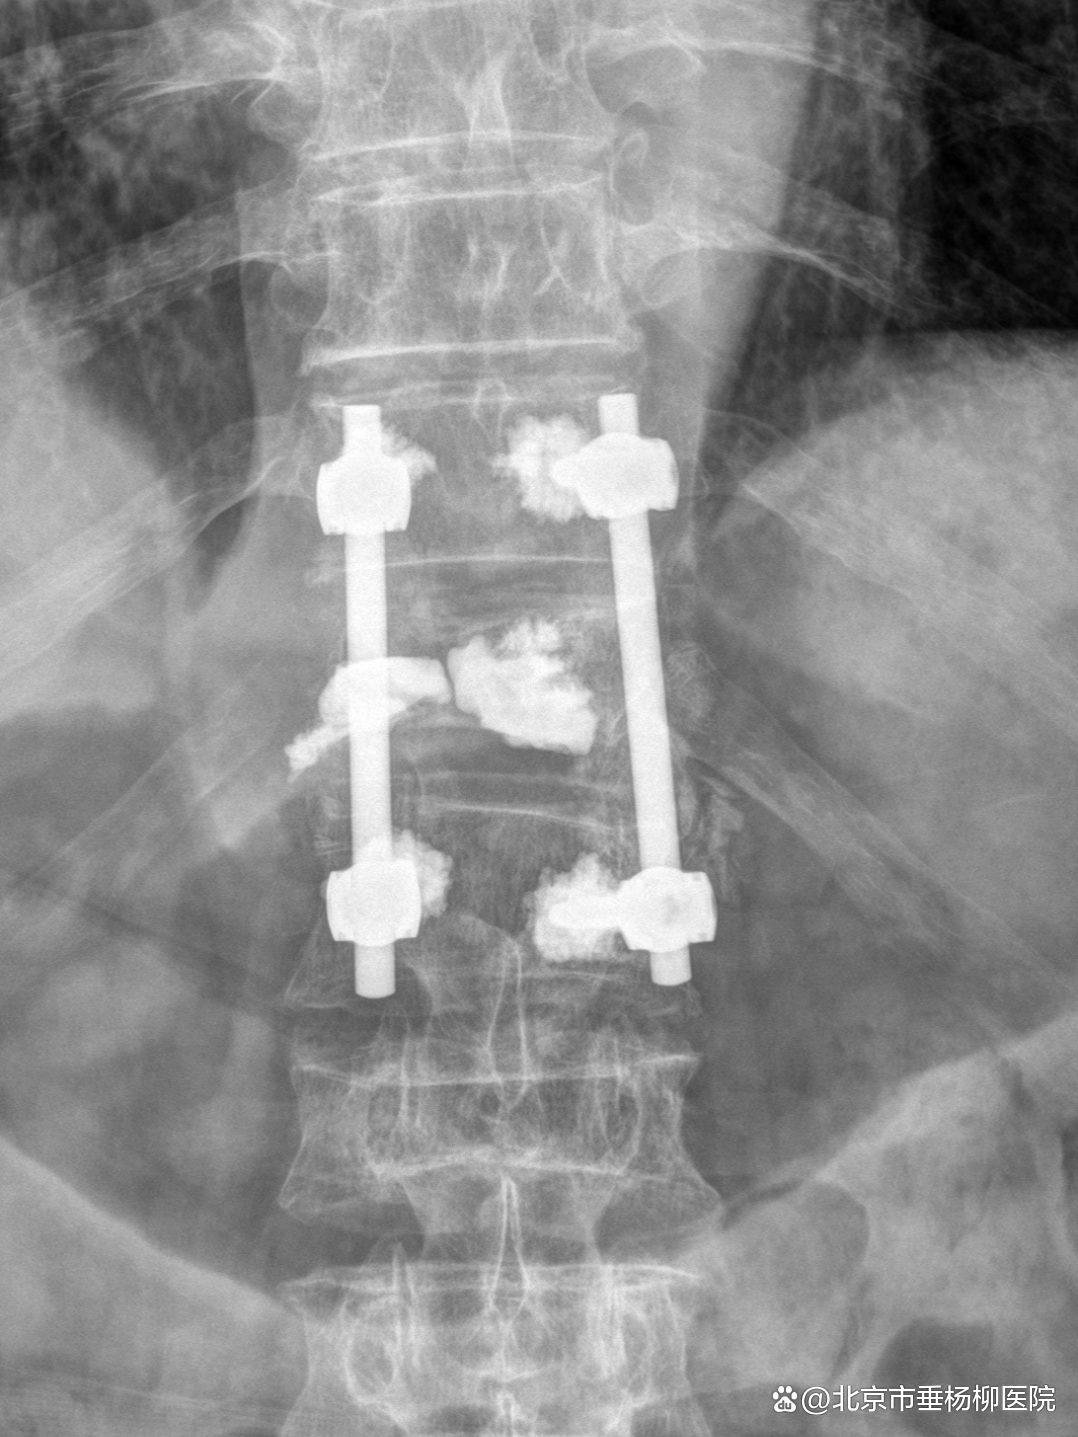

手术当日,姜树东会同脊柱外科(骨四科)主治医师梁得华在全麻下为患者进行后路胸椎椎板切除椎管减压、T12椎体强化术、T11、L1椎弓根钉内固定术、植骨融合术。手术过程顺利。术后患者恢复良好,腰背部显著缓解,在支具保护下可以进行常规活动。患者在术后1周顺利出院,后续接受抗肿瘤相关治疗。

▲术后